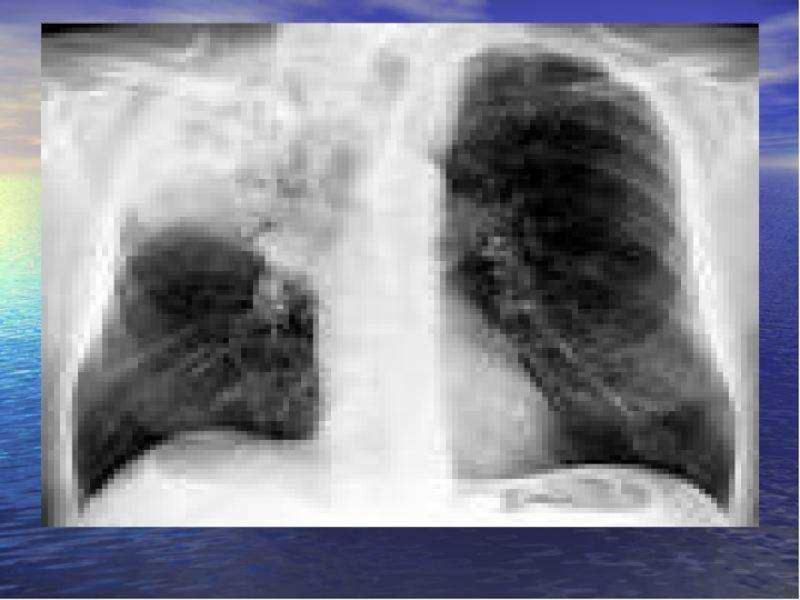

Слайд 51Интерстициальная аденовирусная пневмония

Острая интерстициальная пневмония (вирусная, атипичная). Отмечается значительное усиление легочного

рисунка, корни не изменены, плевра уплотнена. По мере прогрессирования болезни на рентгене становятся видны очаговые затемнения в нижних и средних отделах легких.

Интерстициальная аденовирусная пневмонияОстрая интерстициальная пневмония (вирусная, атипичная). Отмечается значительное усиление легочного рисунка, корни не изменены, плевра уплотнена.